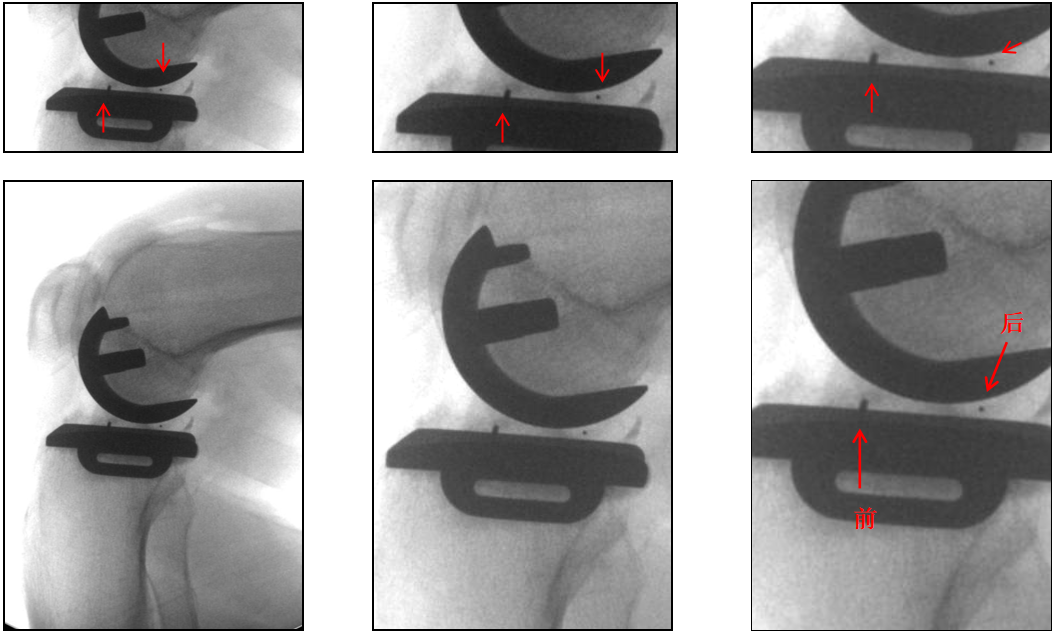

标准正侧位片拍摄方法(术前透视)

在前后位投照中,透视监控下调整X线束和下肢位置,直到胫骨假体完全前后端一致(end on)后拍X光片。

光束与正交平面对准( 水平底板与垂直侧壁和龙骨 ),从而提供准确性和重现性高的x光片。

在侧位投照中,膝关节屈曲20-30°,X射线束以股骨假体为中心,平行于地板。

胫骨假体不能提供任何垂直表面 ,水平面又被侧壁遮挡,所以侧位不如前后位精确性和重复性高。

辨认bearing内的标识(X-ray侧位)

bearing 内的标识:点和线段“ .—. ”线段显示为“—”在前,点显示为“.”在后

辨认bearing内的标识(透视片侧位)

bearing 内的标识:点和线段“ .—. ” 线段显示为“—”在前;点显示为“.”在后